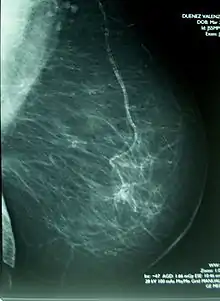

La mamografía o mastografía consiste en una exploración diagnóstica de imagen por rayos X de la glándula mamaria, mediante aparatos denominados mamógrafos (en dosis de alrededor de 0,7 mSv). Estos aparatos disponen de tubos de emisión de rayos X especialmente adaptados para conseguir la mayor resolución posible en la visualización de las estructuras fibroepiteliales internas de la glándula mamaria.

La capacidad de identificación de lesiones de mínima dimensión ha preconizado la utilización de la mamografía en revisiones sistemáticas para detectar tumores antes de que puedan ser palpables y clínicamente manifiestos (cribage mamográfico). Este diagnóstico, efectuado en una fase muy precoz de la enfermedad, suele asociarse a un mejor pronóstico de curación, así como a la necesidad de una menor agresividad del tratamiento para el control del cáncer.

Los radiólogos usan un método estándar para interpretar y comunicar los resultados de la mamografía, que actualmente se considera el idioma universal en el diagnóstico de la patología mamaria. Cuando detectan una lesión sospechosa de cáncer, la clasifican dentro de una categoría de BI-RADS (Breast Imaging-Reporting and Data System), las primeras etapas I y II son benignas, la III es probablemente benigna, mientras la IV y V aumenta la probabilidad de que sean malignas. Este sistema permite estandarizar la terminología del informe mamográfico y categorizar las lesiones estableciendo el grado de sospecha y asignar la actitud a tomar en cada caso. En muchas ocasiones la mamografía puede revelar lesiones malignas sin que estas se palpen clínicamente.[9][10]